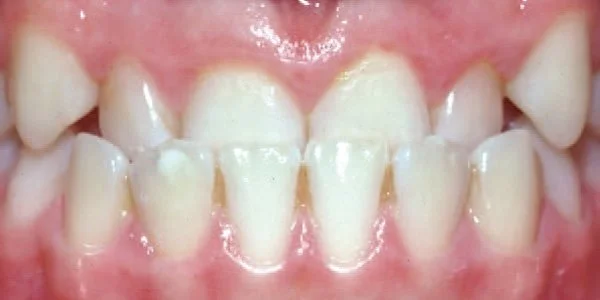

Crowding

Teeth are out of alignment due to lack of space